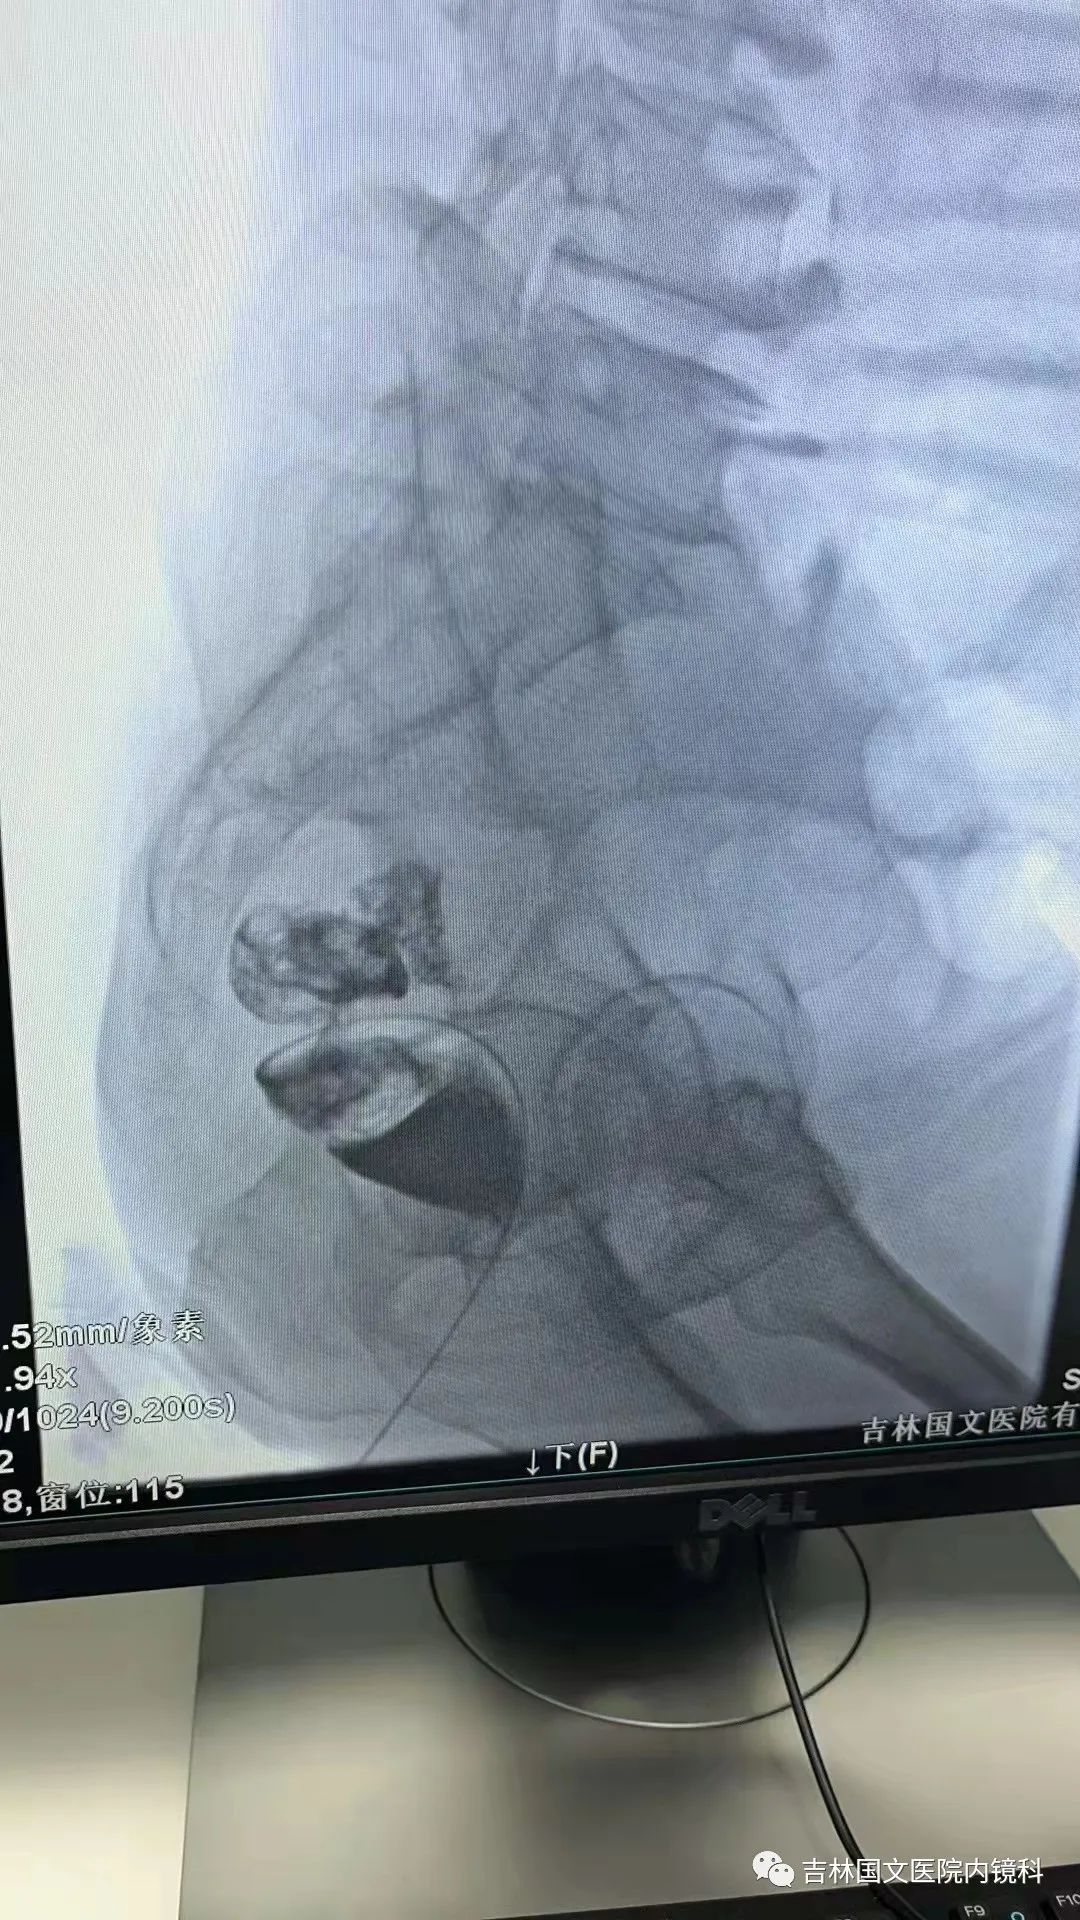

這是一位腸癌的患者,腫物生長在乙狀結(jié)腸,將腸腔堵得只剩一個小孔,糞便自然很難通過,腸梗阻的癥狀使患者十分難受,已多天未排氣排便,患者十分瘦削,開始侯主任未借助任何工具探查一番,結(jié)果就是腸道太迂曲了,實(shí)在無法順利將導(dǎo)絲置入,通過邢主任使用腸鏡在前面引路一直到達(dá)病變部位,這時候侯主任將帶有外套管的導(dǎo)絲從活檢口插入,外套管抵在小孔處,導(dǎo)絲順利進(jìn)入,第一步成功。第二步就是將支架順著導(dǎo)絲送入指定位置,又是一大難關(guān),導(dǎo)絲十分軟,缺乏支撐力,腸道的彎曲十分陡峭,一用力支架抵在腸道低處,患者痛感極強(qiáng),只能另想辦法,嘗試多次后,在兩位主任的豐富經(jīng)驗(yàn)和堅持不懈的努力下,支架順利置入,為患者解除了痛苦。